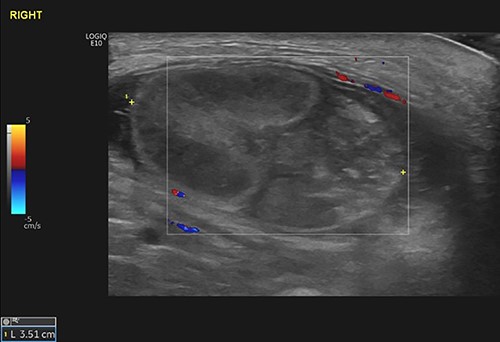

Subsequent ultrasound of the scrotum (Fig. 2) showed a swollen, heterogeneous and ischemic right testicle that was fixed in the groin suggesting torsion on a background of UT.

The right testicle was recognized as a 27 × 37 mm heterogeneous mass in the right groin, demonstrating no blood flow. The epididymis was also found bulky. The findings were consistent with the clinical diagnosis of TT in the background of UT.